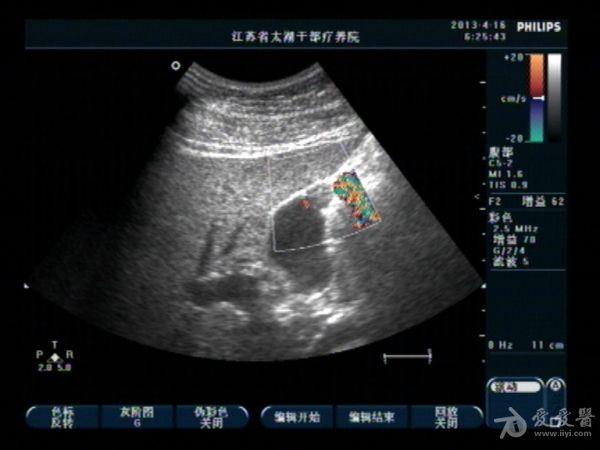

胆囊底部稍低回声区,胆泥沉积?胆囊癌不像吧?,请分析

男性,40,无右上腹痛

可以用高频探头看看,更 清晰!